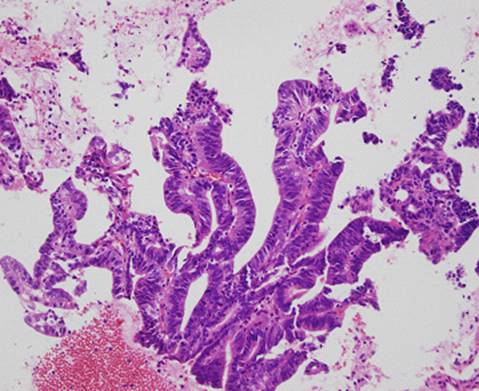

4. さらに別の細胞集団ですが、間質を中心に腺細胞が乳頭状の集塊を形成して認められました。

左下のセルブロック標本でも癌細胞が乳頭状に増生しています。